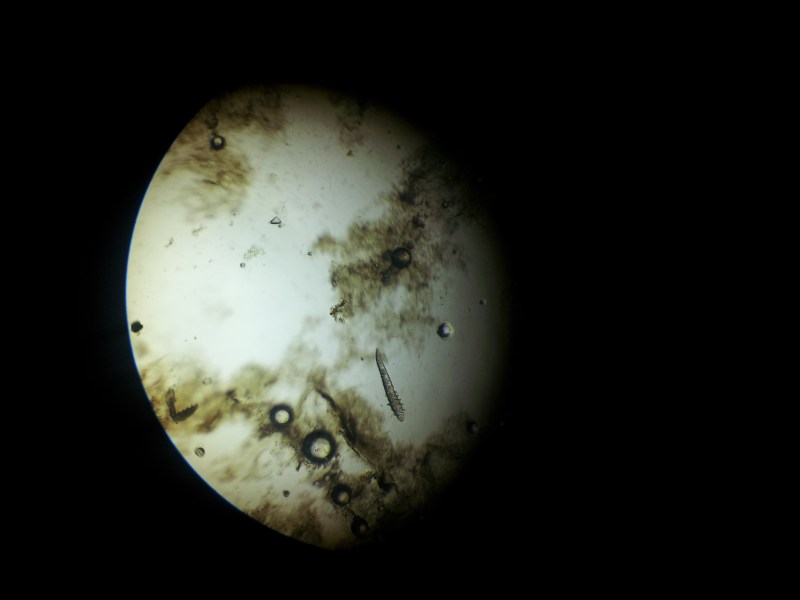

zdjęcie 1